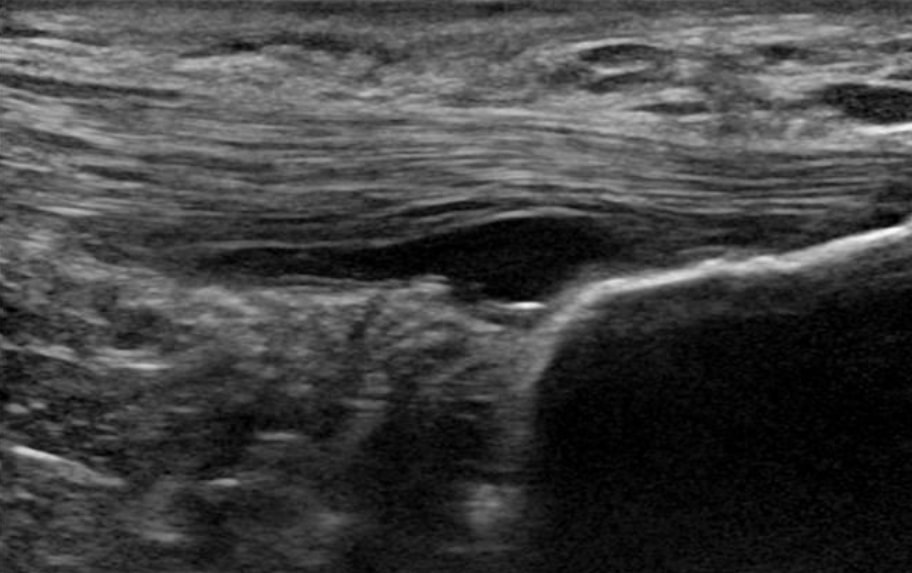

1. Ноцицептивният двигател на болката в сухожилията е неизвестен. Патологията, която се вижда при визуализация, не е причината за болката. Васкуларността не е източник на болката, а само маркер за дегенерация на сухожилията. Освен това няма сетивни нерви дълбоко в сухожилието, а в периферията около него. Нервите, които прорастват в патологично сухожилие, са симпатикови, а не сетивни. Накрая, централната сенсибилизация вероятно е по-малък проблем при патологията на долните крайници в сравнение с патологията на горните крайници(Plinsinga et al. 2015, Plinsinga et al. 2018).

2. Не сме в състояние да възстановим/излекуваме дегенеративната патология на сухожилията. С други думи, никаква операция, никаква терапия с ударни вълни, никакви инжекции и дори упражнения не са в състояние да възстановят или излекуват дегенерирало сухожилие. Докинг и др. (2019) смятат, че при слаба способност да усещат натоварване на опън клетките в дегенеративната част на сухожилието могат да бъдат недостатъчно стимулирани и да не получават необходимите механични стимули за ремоделиране, което обяснява ограничената способност на патологичното сухожилие да се ремоделира и нормализира. Макар да си мислите, че това може да е лоша новина, добрата новина е, че не е и необходимо. Проучване на Tsehaie и др. (2017) показва, че 24-седмичните ексцентрични упражнения за ахилесовото сухожилие не водят до промени извън границите на откриваемото изменение в сухожилието, но въпреки това пациентите се подобряват. Те също така установиха, че параметърът на МРТ в началото на изследването предсказва промяната в симптомите, така че дори ако МРТ изглежда ужасно, това няма значение.

6. Патологичното сухожилие има по-добра структура от нормалното сухожилие(Docking et al. 2015). Това означава, че можем да натоварим тези сухожилия, защото разполагаме с много добра тъкан. Не са необходими никакви терапии за патологията на сухожилията, тъй като така или иначе не можем да променим структурата на патологичната част. Поради тази причина Докинг и колегите му измислят цитата "Лекувайте поничката, а не дупката" - с други думи, съсредоточете се върху здравата структура, а не върху патологичната част.

Патологичното сухожилие има по-добра структура от нормалното сухожилие (Docking et al. 2015)